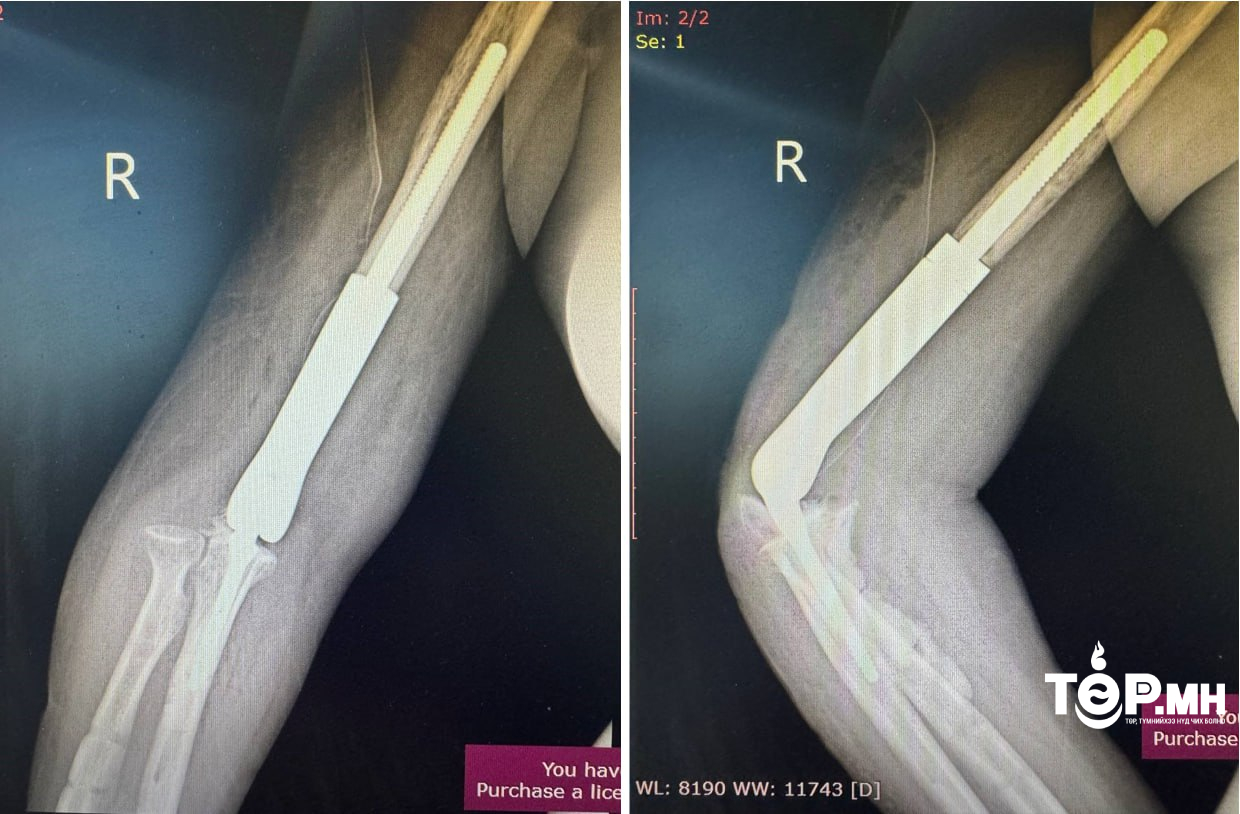

Уг мэс засал нь авто ослын дараах атгаалын чөмөгт ясны доод хэсэг бяцарч, үйрмэг мэт болон хугарч, эргэн сэргэшгүй болж дутмагшил үүссэн (10см орчим) ясыг орлуулах, үеийг орлуулсан, нийлмэл тохойн хиймэл үе бүхий имплантыг суурилуулан гарын хөдөлгөөнийг бүрэн сэргээж, амьдарлын чанарыг сайжруулах мэс засал эмчилгээ юм.